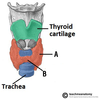

What is A?

Transverse process

What is B?

Body of vertebrae